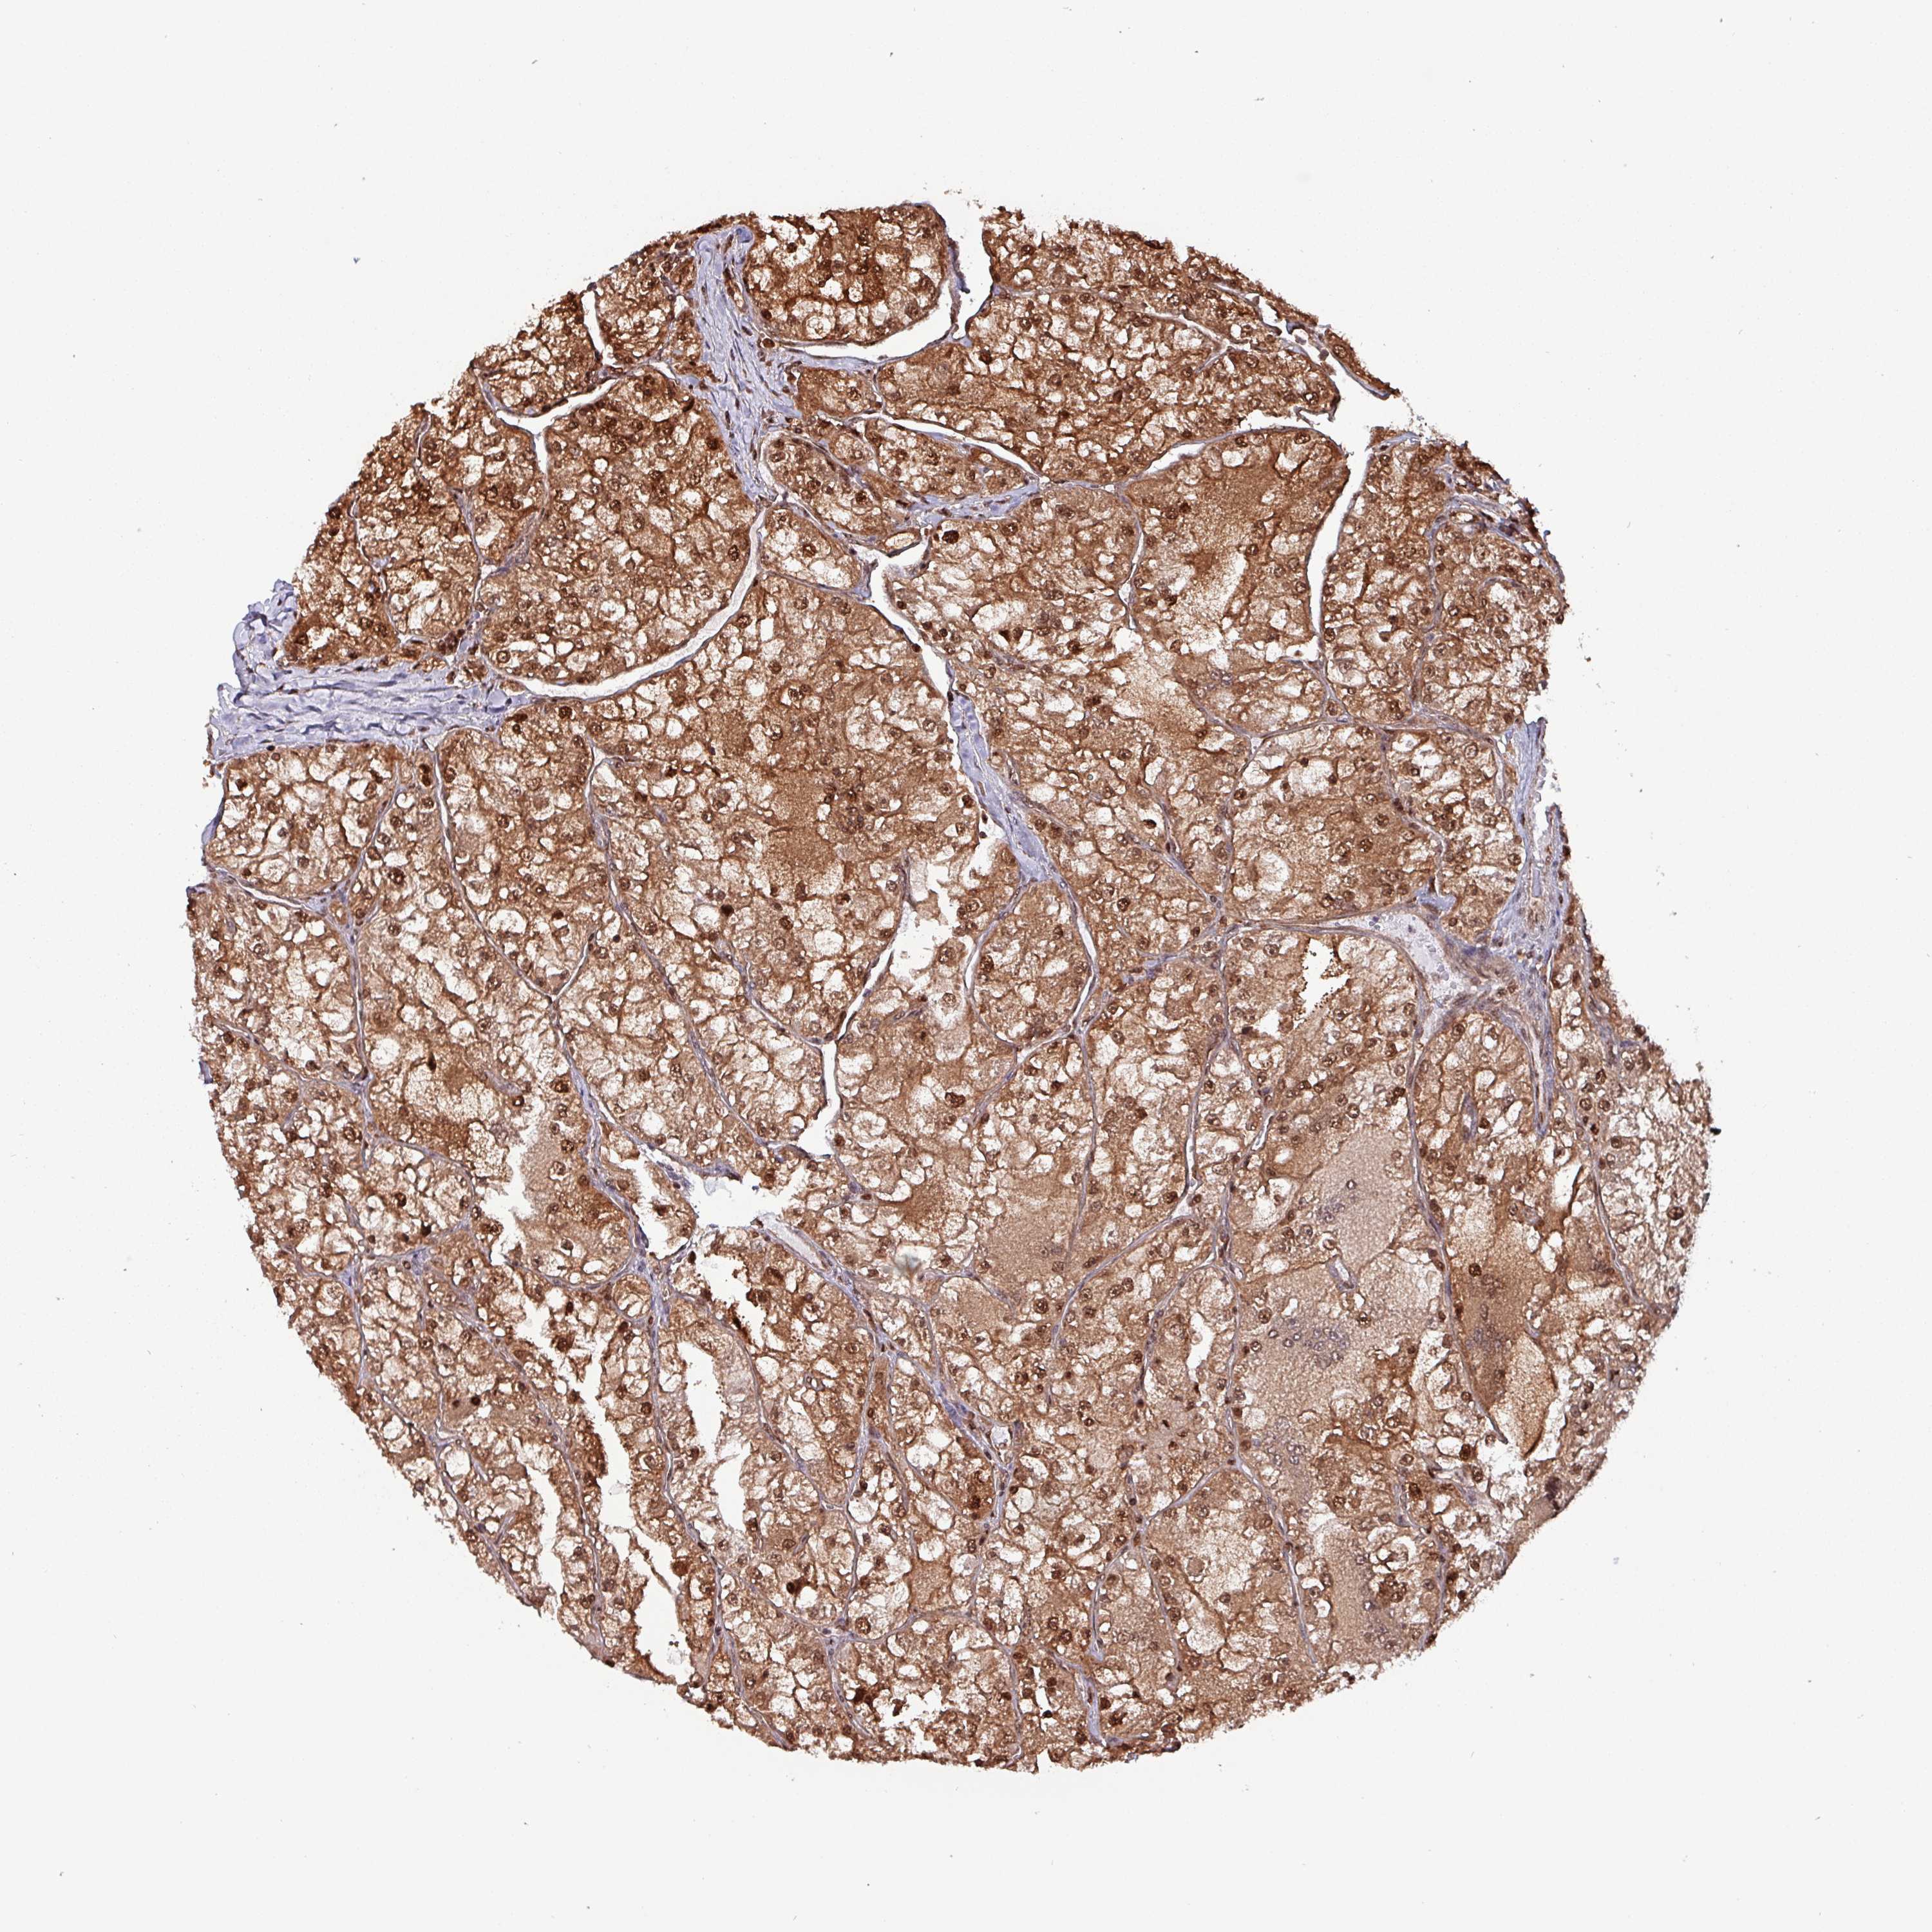

KIDNEY RENAL CLEAR CELL CARCINOMA (TCGA) - Interactive survival scatter ploti

The Survival Scatter plot shows the clinical status (i.e. dead or alive) for all individuals in the patient cohort, based on the same data that underlies the corresponding Kaplan-Meier plots. Patients that are alive at last time for follow-up are shown in blue and patients who have died during the study are shown in red.

The x-axis shows the expression levels (FPKM) of the investigated gene in the tumor tissue at the time of diagnosis. The y-axis shows the follow-up time after diagnosis (years). Both axes are complimented with kernel density curves demonstrating the data density over the axes. The top density plot shows the expression levels (FPKM) distribution among dead (red) and alive patients (blue). The right density plot shows the data density of the survived years of dead patients with high and low expression levels respectively, stratified using the cutoff indicated by the vertical dashed line through the Survival Scatter plot. This cutoff is automatically defined based on the FPKM cutoff that minimizes the p-score. The cutoff can be changed by dragging the vertical line or by entering a cutoff value in the square labeled "Current cut-off".

Under the Survival Scatter plot the p-score landscape (black curve; left axis) is shown together with dead median separation (red curve; right axis). Dead median separation is the difference in median mRNA expression between patients who have died with high and low expression, respectively. It is calculated as follows: median FPKM expression of dead patients with high expression - median FPKM expression of dead patients with low expression. This is intended to aid the user in visually exploring custom cutoffs and the associated p-scores and dead median separation.

Individual patient data is displayed and can be filtered by clicking on one or more of the category buttons on the top of the page. Categories describing expression level and patient information include: high, low, alive, dead, female, male and tumor stages. The scale of the x-axis can be toggled between linear and log-scale by clicking on the "x log" button. Mouse-over function shows TCGA ID, patient information and mRNA expression (FPKM) for each patient.

& Survival analysisi

Kaplan-Meier plots summarize results from analysis of correlation between mRNA expression level and patient survival. Patients were divided based on level of expression into one of the two groups "low" (under cut off) or "high" (over cut off). X-axis shows time for survival (years) and y-axis shows the probability of survival, where 1.0 corresponds to 100 percent.

PSMB8 is not prognostic in Kidney Renal Clear Cell Carcinoma (TCGA)

Best expression cut offi

Based on the FPKM value of each gene, patients were classified into two groups and association between prognosis (survival) and gene expression (FPKM) was examined. The best expression cut-off refers the FPKM value that yields maximal difference with regard to survival between the two groups at the lowest log-rank P-value. Best expression cut-off was selected based on survival analysis .

When clicking on this number, the vertical dashed line indicating cut-off, the interactive survival plot, and the Kaplan-Meier curve will be adjusted to show results based on the best expression cut-off.

: 26.55

Median expressioni

Median expression refers to the median FPKM value calculated based on the gene expression (FPKM) data from all patients in this dataset. When clicking on this number, the vertical dashed line indicating cut-off, the interactive survival plot, and the Kaplan-Meier curve will be adjusted to show results based on the median expression.

: N/A

Median follow up timei

Median follow up time refers to the median time (years) after diagnosis with this type of cancer, based on clinical data from all patients in this dataset.

P scorei

Log-rank P value for Kaplan-Meier plot showing results from analysis of correlation between mRNA expression level and patient survival.

N/A

5-year survival highi

5-year survival for patients with higher expression than the expression cutoff.

For melanoma and glioma, 3-year survival is shown.

5-year survival lowi

5-year survival for patients with lower expression than the expression cutoff.

TCGA RNA samplesi

RNA-seq data is reported as average FPKM (number Fragments Per Kilobase of exon per Million reads), generated by the The Cancer Genome Atlas (TCGA) .

Normal distribution across the dataset is visualized with box plots, shown as median and 25th and 75th percentiles. Points are displayed as outliers if they are above or below 1.5 times the interquartile range. FPKM values of the individual samples are presented next to the box plot.

Average pTPM 23.3

Number of samples 521